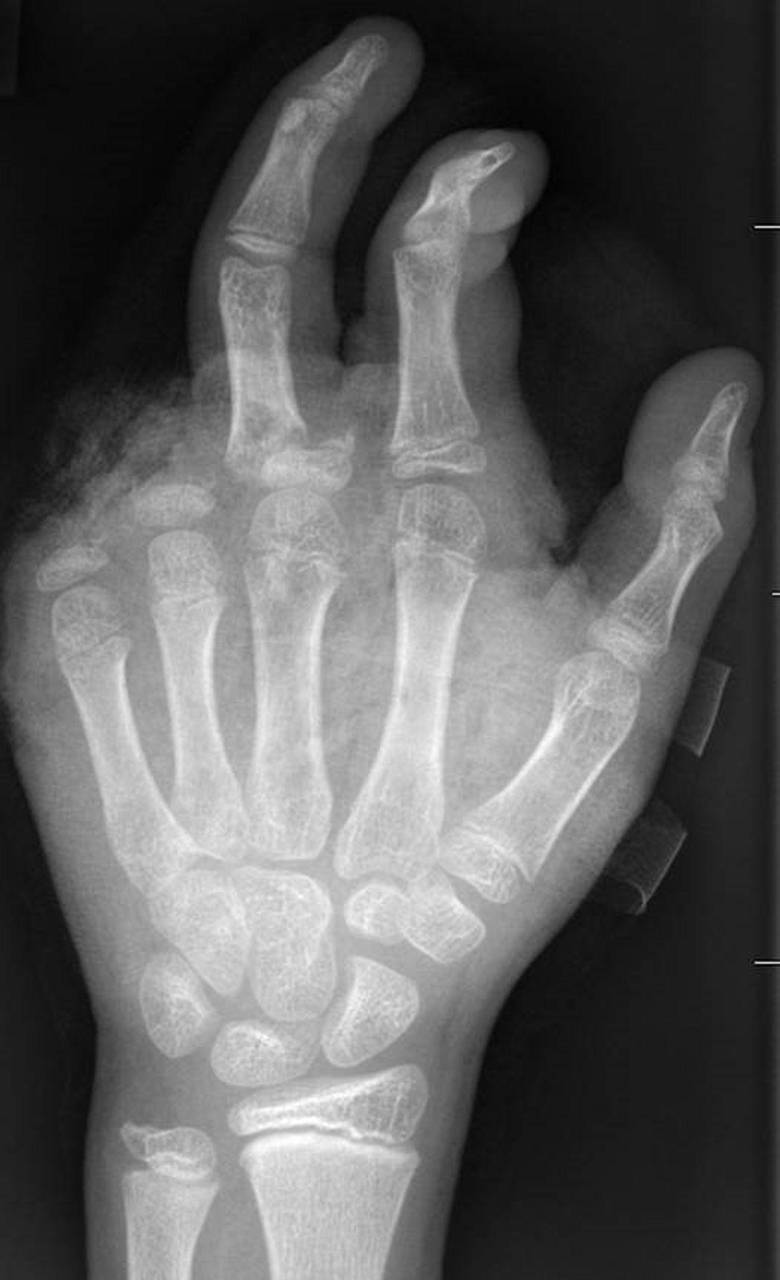

Für eine neue Dimension habe im vergangenen Jahr das illegale Abbrennen von Kugelbomben gesorgt. «Die Patienten mit Verletzungen durch Kugelbomben weisen sehr viel stärkere Verletzungsmuster auf, die auch den ganzen Körper betreffen, weil diese Explosion ungerichtet stattfindet. Und das sind nicht nur Hände und Gesichter, sondern auch Bauch, Beine.» Alle Körperareale seien gleichermaßen gefährdet.

Vergangenes Jahr wurde ein Siebenjähriger in Berlin schwer durch eine Kugelbombe verletzt und musste Dutzende Male operiert werden. Er überlebte nur knapp.